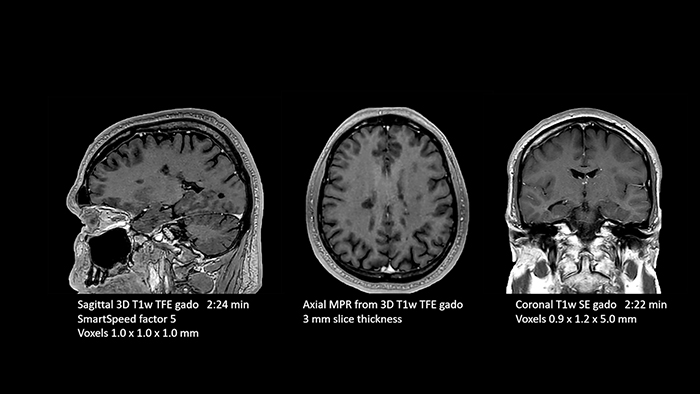

Dr. Schröter points out that a more confident diagnosis requires high-quality images with more diagnostic information. “Philips SmartSpeed provided that to us. AI denoises the clinical images without losing any important data, resulting in high-resolution images. It keeps all the information we need and makes the images better. We can apply SmartSpeed to almost all sequences. That is a big step forward! We use it for example in 3D imaging and in diffusion-weighted imaging, to dramatically reduce scan time or increase image resolution, which is quite useful. There are small lesions that we would certainly have seen without SmartSpeed, however it would have taken us longer to properly diagnose. In 3D MSK images with extremely high resolution, we uncover the finest anatomical structures and can thus report very detailed findings.”